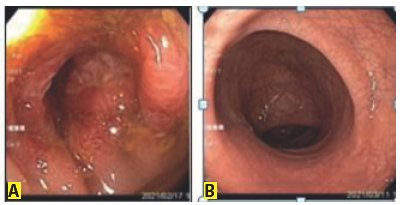

Paciente mujer de 77 años de edad procedente de La Paz Bolivia, región a 3 650 m.s.n.m. con constipación ocasional, presenta dolor cólico súbito en flanco izquierdo, proctalgia, sensaciones de urgencia para defecar y de cuerpo extraño en recto, escasa eliminación de gases y heces, no rectorragia ni hematoquecia. En los primeros días de internación se realiza rectosigmoidoscopía flexible y posterior colonoscopia que muestran hemorroides internas GII y a 35 cm del margen anal un tumor de sigmoides circunferencial friable, con superficie vascularizada irregular con NBI (Imágenes de banda estrecha), luz de 14 mm, se toman biopsias ( Figura 1-A).

A. Tumor de sigmoides circunferencial friable, superficie vascularizada irregular con NBI, luz de 14 mms (Diagnóstico endoscópico: adenocarcinoma vs. Enfermedad inflamatoria intestinal)

B. Rectosigmoidoscopía normal

Reingresa a los 4 días con el mismo dolor en flanco izquierdo, poca evacuación, nueva rectosigmoidoscopia normal ( Figura 1-B), se realiza radiografía contrastada de colon (colon por enema) que muestra dolicomegacolon con torsión de sigmoides en roseta ( Figura 3), motivo de la colitis isquémica. Coloproctología realiza laparotomía, observa dolicomegasigmoide, descendente y sigmoides elongados y enrollado a nivel de unión rectosigmoidea y ángulo esplenocolónico con mesosigmoiditis retráctil, isquemia de sigmoides, procede a colectomía izquierda con anastomosis terminoterminal con stapler circular Nº33 más lavado, drenaje de cavidad y apendicectomía incidental tipo Pouchet ( Figura 3), no se realiza cirugía laparoscópica por tiempo de pandemia COVID-19. Histopatología de colon con cambios isquémicos, inflamatorios, edema de pared, plexo nervioso normal ( Figura 2-B). Con este tratamiento definitivo, la evolución fue favorable con buen pronóstico.